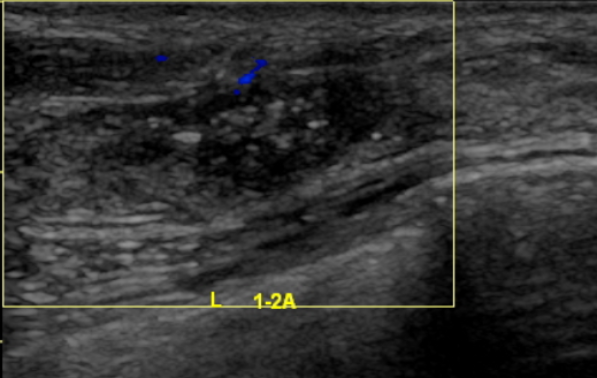

2021-6-9乳腺及腋窝淋巴结超声:左侧乳腺外上象限见大小约45*21mm低回声团块,边界不清,形态不规则,肿块前缘达皮肤层,内回声不均匀,内见多枚杂乱强光点,可见血流信号,测其动脉血流RI0.76。余双侧乳腺腺体形态、结构未见异常。左侧腋窝见多枚低回声结节,边界清,形态饱满,有包膜,内见多发强光点,较大者约13*10mm,内可见血流信号。右侧腋窝未见肿大淋巴结回声。

影像诊断:左侧乳腺低回声团块(BI-RADS:5类,考虑浸润性Ca);左侧腋窝多发异常肿大淋巴结。

图1.乳腺B超(2021-6-9)